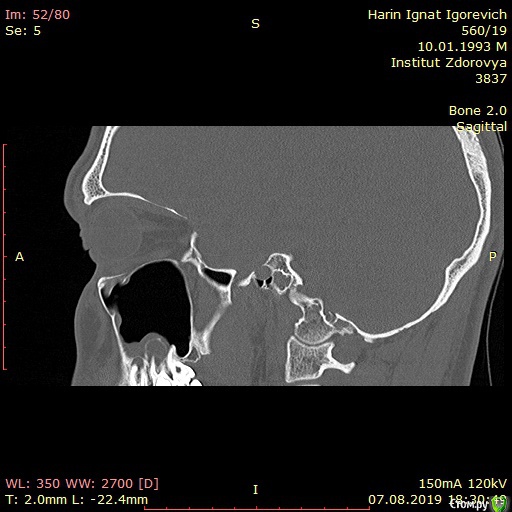

Игнат46 Опубликовано 9 декабря, 2019 Поделиться Опубликовано 9 декабря, 2019 Город Москва. Одонтогенные кисты у корней 16,17 зубов Добрый день. Ищу клинику и специалиста для лечения кист.Сделал КТ пазух носа, и обнаружились кисты на корнях двух зубов. Ничего не беспокоило, прошел месяц, а сейчас уже второй день чувствую боль при нажатии на десну в этой области и некоторую опухлость . Ссылка на комментарий